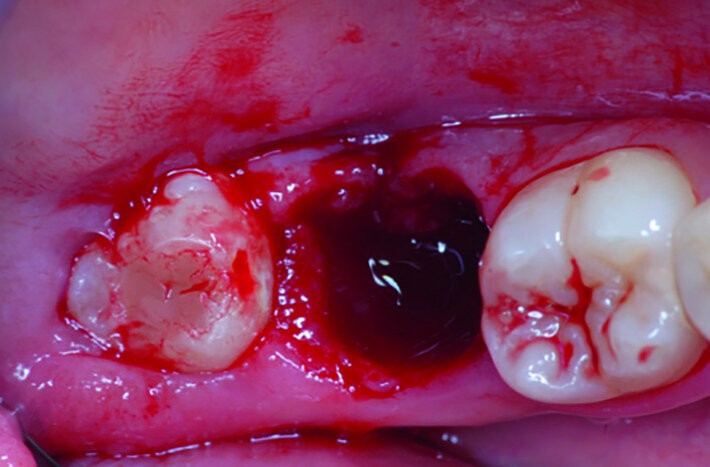

Fig. 17a: Clinical images: Extraction site of fractured tooth #47.

Fig. 17b: Clinical images: Tooth #48 positioned in the extraction site.

The left mandibular second molar of a 35-year-old female patient had been compromised because of a vertical root fracture and a large periapical lesion was present. After explanation and informed consent, the treatment was scheduled. The right mandibular third molar was preferred as a donor to the left mandibular third molar because of a more compatible anatomy and for an easier stabilisation. After local anaesthesia of both the donor and the recipient sites with 2 per cent mepivacaine with 1:100,000 adrenaline, the left mandibular second molar was extracted and the alveolus debrided. Then the donor tooth was atraumatically extracted, quickly repositioned in the recipient site and stabilised with sutures at about 1.5–2.0 mm of infraocclusion. An antibiotic (amoxicillin/clavulanic acid, 1 g, by mouth twice a day for five days) and a non-steroidal anti-inflammatory drug (ibuprofen, 600 mg, by mouth twice a day for five days) were prescribed, along with rinses with 0.2 per cent chlorhexidine. The sutures were removed after two weeks and endodontic treatment was performed after three months. The periapical lesion healed and the tooth was fully functional after 12 years (Figs. 14a–d & 15a–d).

A 23-year-old female patient presented with a vertical root fracture of tooth #47. Tooth #48 was transplanted to site #47. The tooth was fully functional after eight years (Figs. 17a–d & 18a–d).